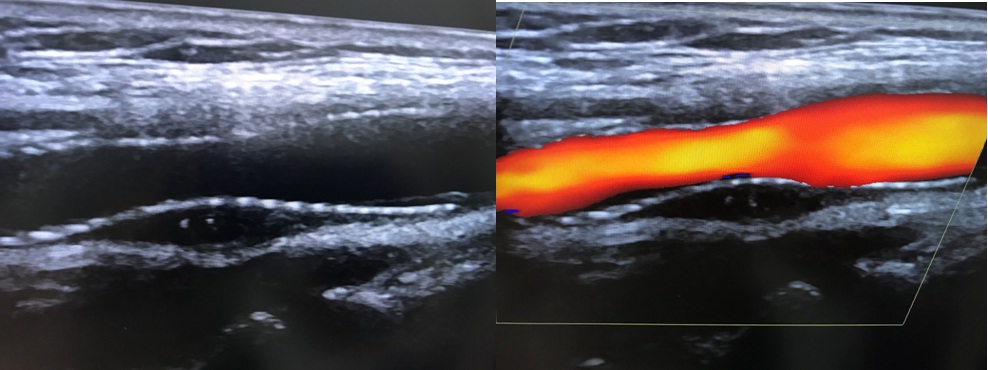

+ Siêu âm Động mạch cảnh: Hẹp động mạch cảnh trong phải đoạn gốc # 70%.

Bệnh nhân tái khám sau 9 tháng, gốc RICA không tái hẹp, stent chưa thấy bất thường